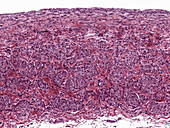

12360983 - Kidney, light micrograph